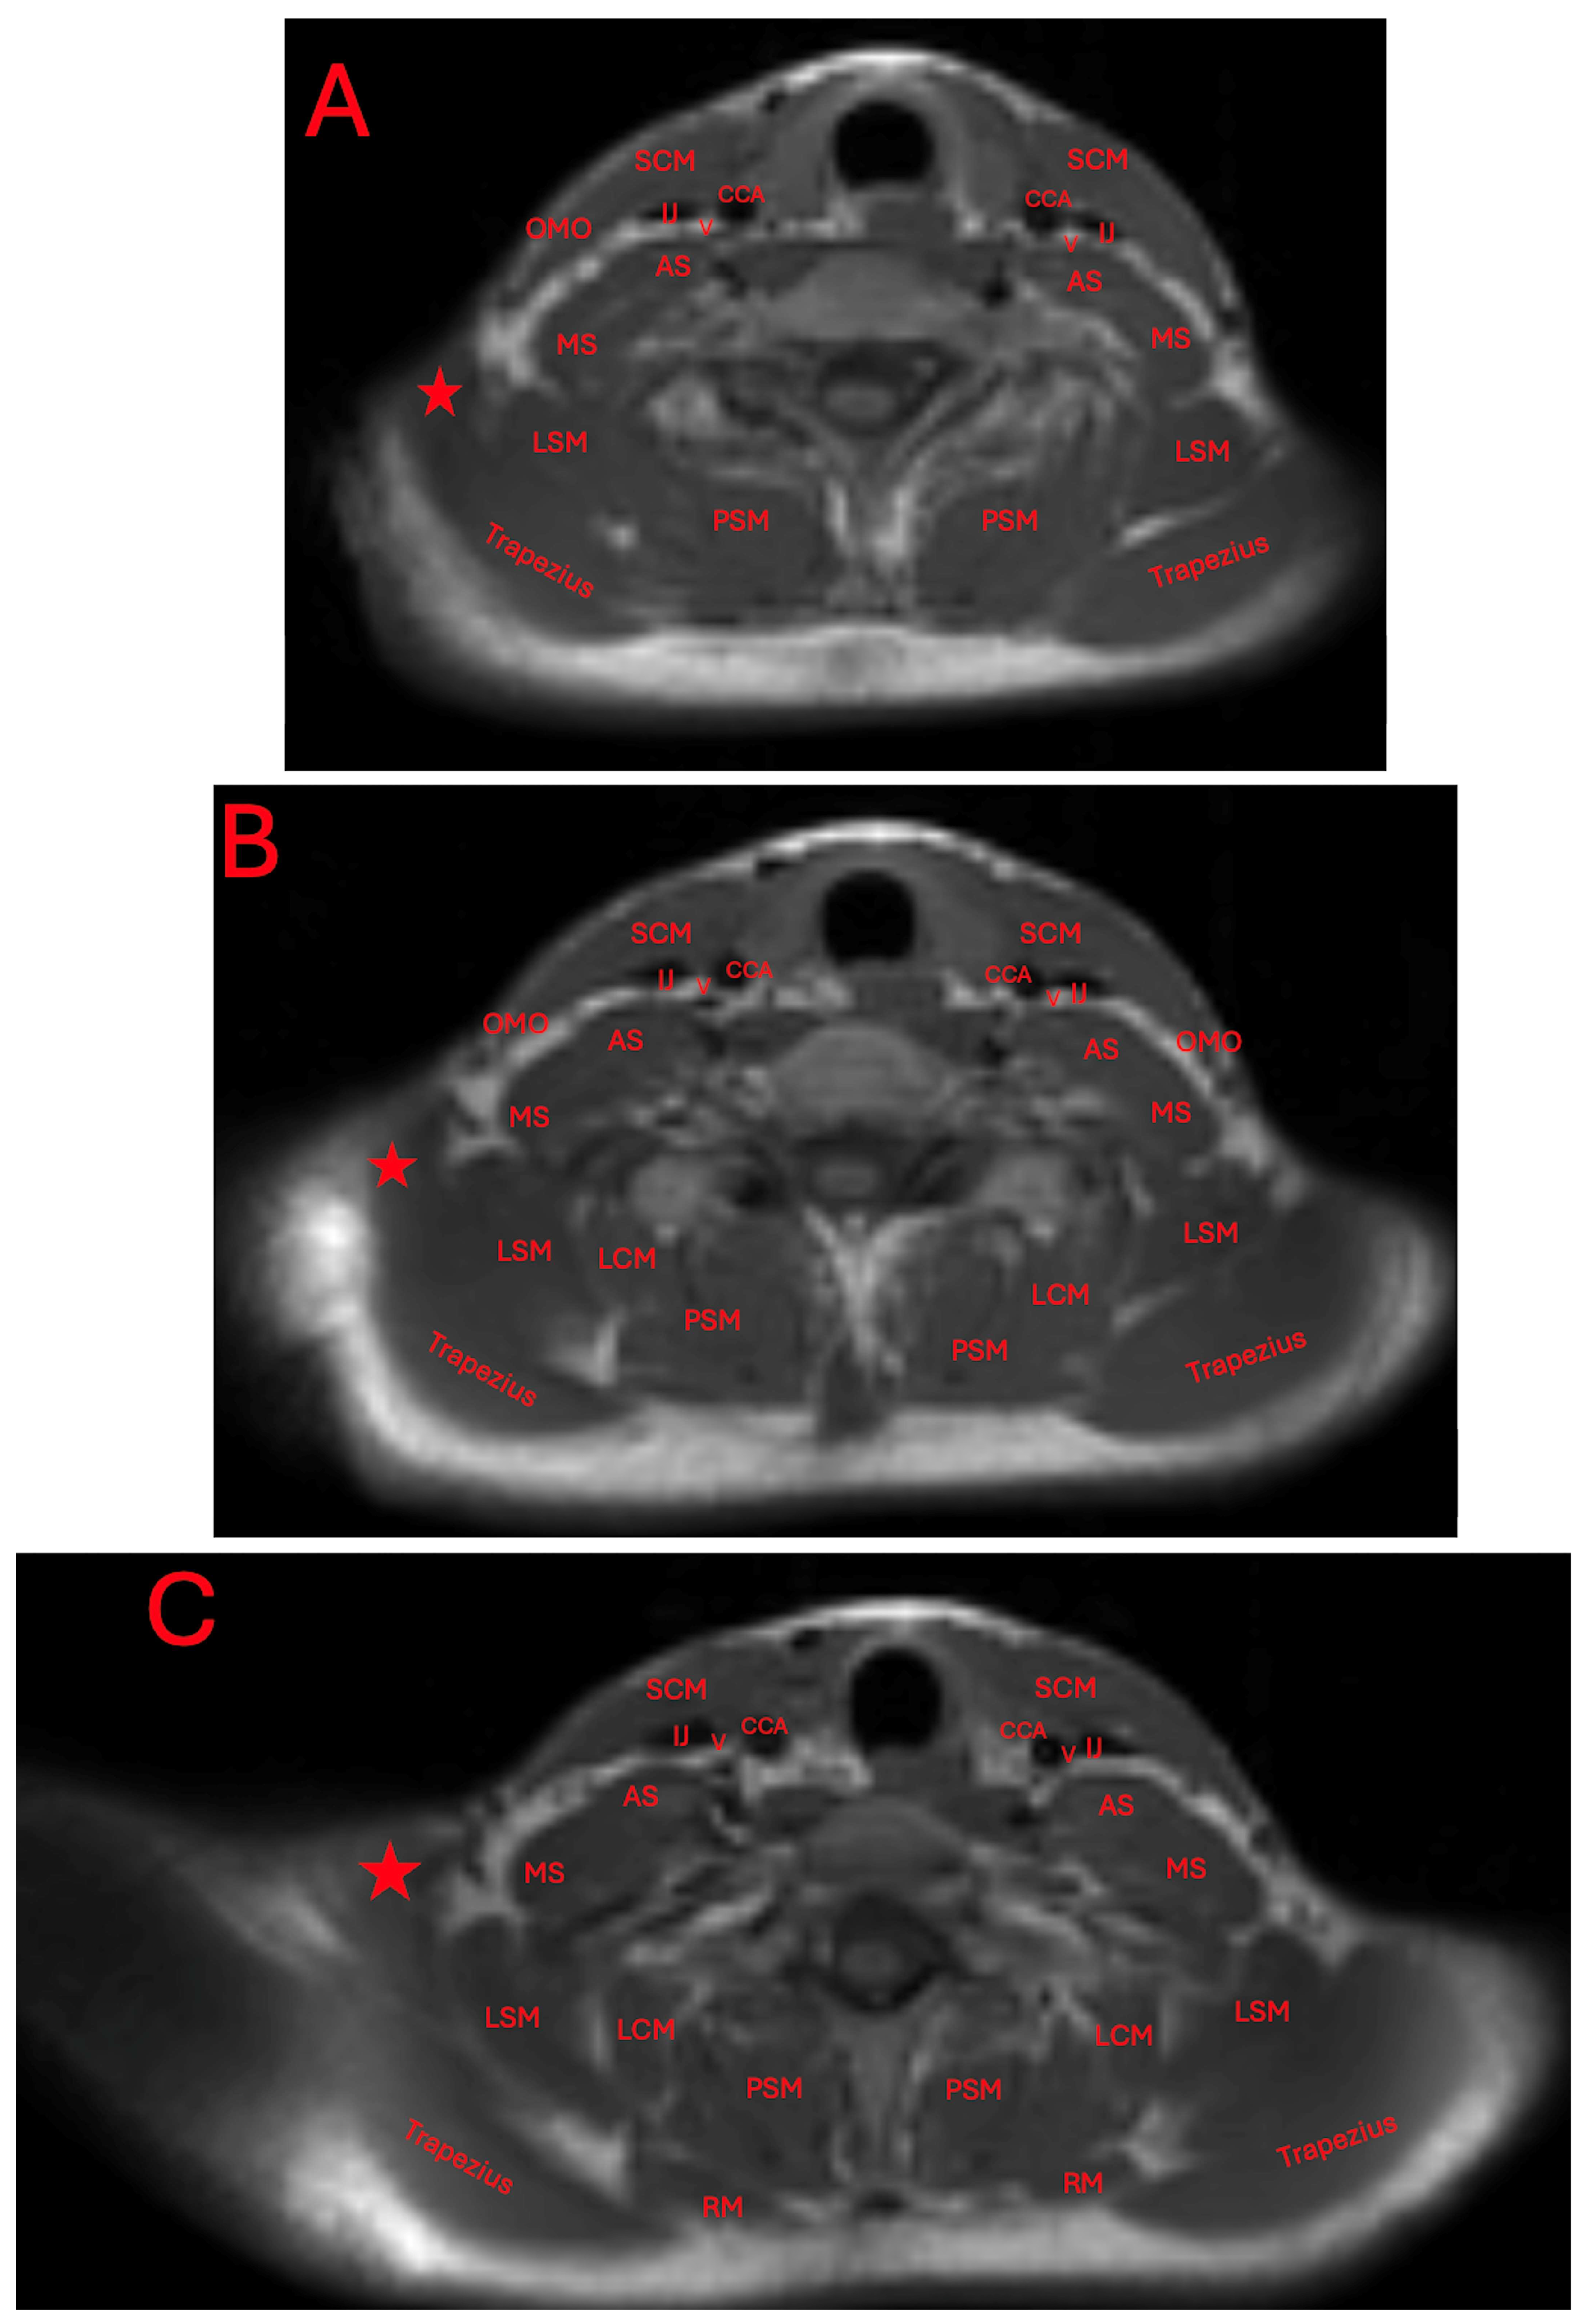

The patient was seen by an outside neurologist who performed an ultrasound of the right neck. This neurologist reported the presence of normal skeletal muscle inserting at the clavicle and blending with the trapezius. They additionally reported a cervical band subjacent to the brachial plexus, and a transverse artery traveling between the upper and middle trunks. An MRI was ordered to further characterize the accessory muscle. Its location was found to be superior to the neurovasculature bundle (Figure 2 and Figure 3).

The presence of this accessory muscle can also be observed adjacently to the trapezius and levator scapulae muscles, and attached to an irregular protuberance of the clavicle (Figure 4A–D).

Figure 4. Axial T1-weighted MRI imaging of the patient’s neck and shoulder (AD). Red stars indicate the position of the levator claviculae muscle. The other abbreviations are the common carotid artery (CCA), vagus nerve (V), internal jugular vein (IJ), sternocleidomastoid (SCM), anterior scalene muscle (AS), middle scalene muscle (MS), omohyoid (OMO), levator scapulae muscle (LSM), longissimus cervices muscle (LCM), paraspinal muscle (PSM), and rhomboid muscle (RM).